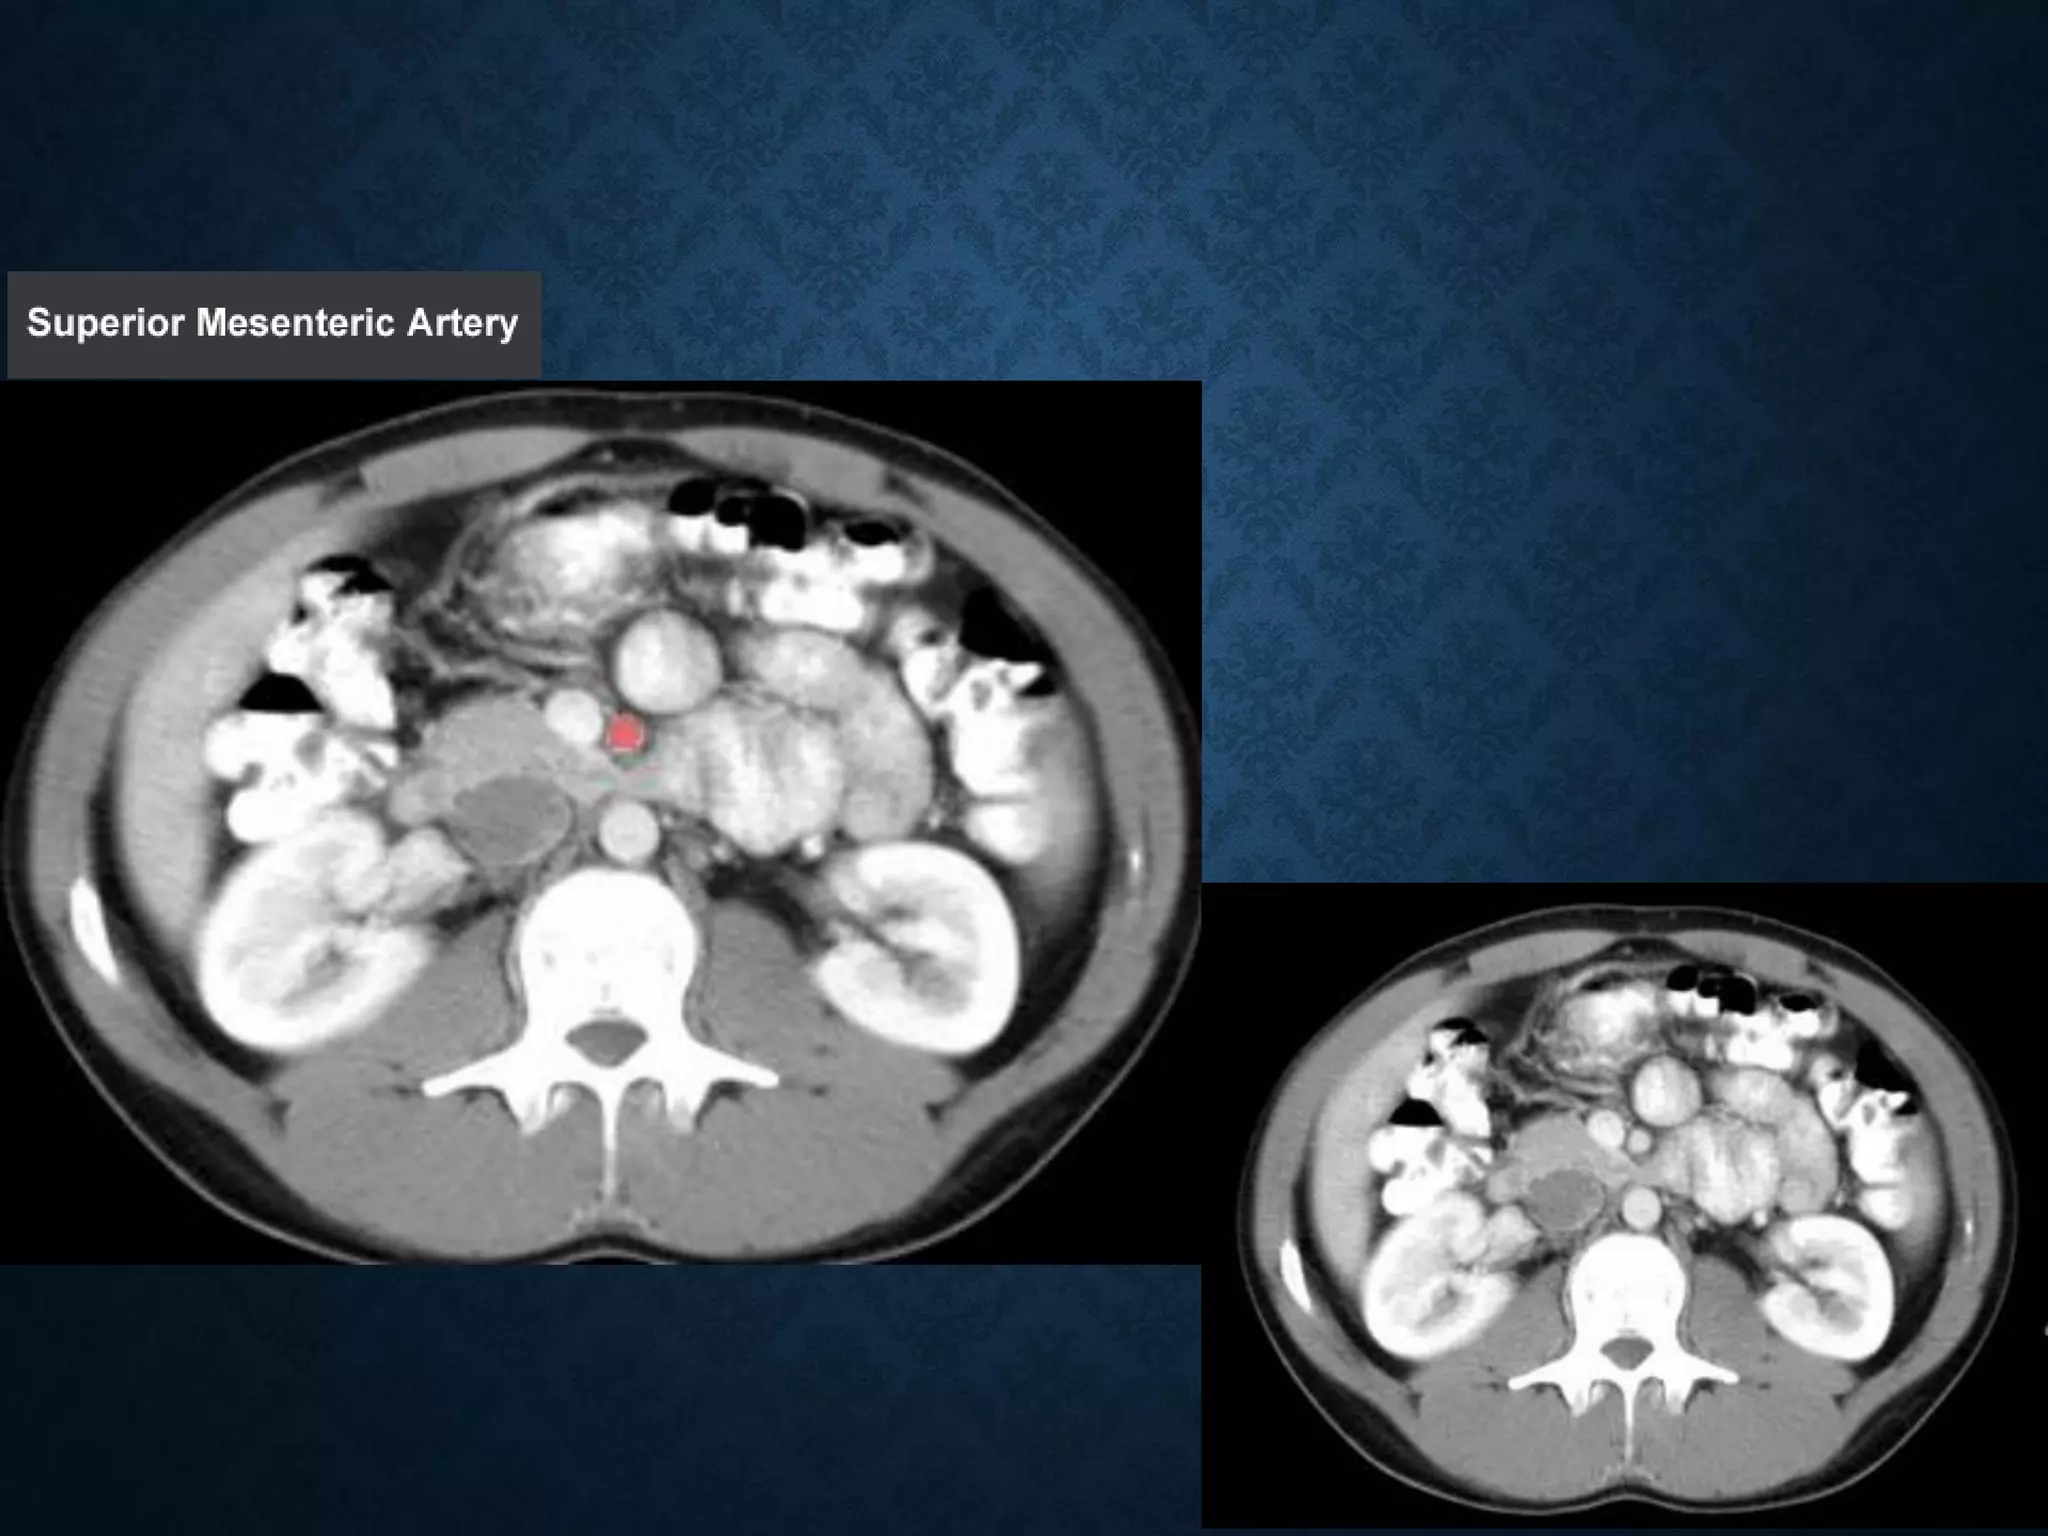

Identify the following structures in the body CT to the right. To view the location of the structure in the image click on

the label at the left and the structure will be indicated in the image. Abdominal CT scans typically begin just above

the diaphragm, so the first slice you see is of the lower chest.

Identify the followingstructures in the body CT to the right. To view the location of the structure in the image click on the label at the left and the structure will be indicated in the image. Abdominal CT scans typically begin just above the diaphragm, so the first slice you see is of the lower chest.

SUPERIOR MESENTERIC VEIN •In anatomy, the superior mesenteric vein (SMV) is a blood vessel that drains blood from the small intestine (jejunum and ileum). • At its termination behind the neck of the pancreas, • the SMV combines with the splenic vein to form the hepatic portal vein. • The SMV lies to the right of the similarly named artery, the superior mesenteric artery, which originates from the abdominal aorta.